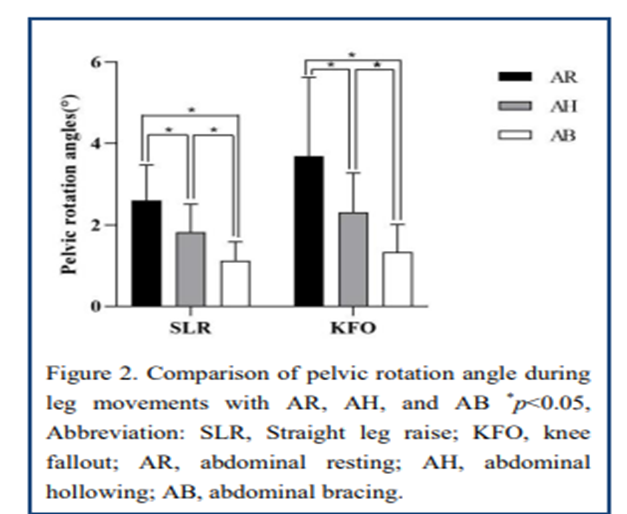

2020년도 연구논문에서는 다리의 무릎을 펴고 신전하는 Active Leg Raise(SLR)동작과

무릎을 구부리고 다리를 거상시키는 Bent Knee Fall out(KFO)동작수행시

Abdominal Hollowing과 Abdominal Bracing 그리고 휴식시를 비교한 논문연구를

언급해보려고합니다.

이 연구에서는 Abdominal Bracing방법이 Abdominal Hollowing방법보다 다리

신전거상(SLR)동작 수행시에 골반의 회전각도가 더 줄어들었다고 언급하고 있습니다.

물론 크레이그리벤슨선생님의 이 칼럼과 앞선 논문에서의 연구결과 에서처럼

Abdominal Bracing의 방법이 골반회전감소와 축강성(Axial Stiffnes)에 도움이 더 되고

Abdominal Hollowing방법은 그 효과가 적을수 있습니다.